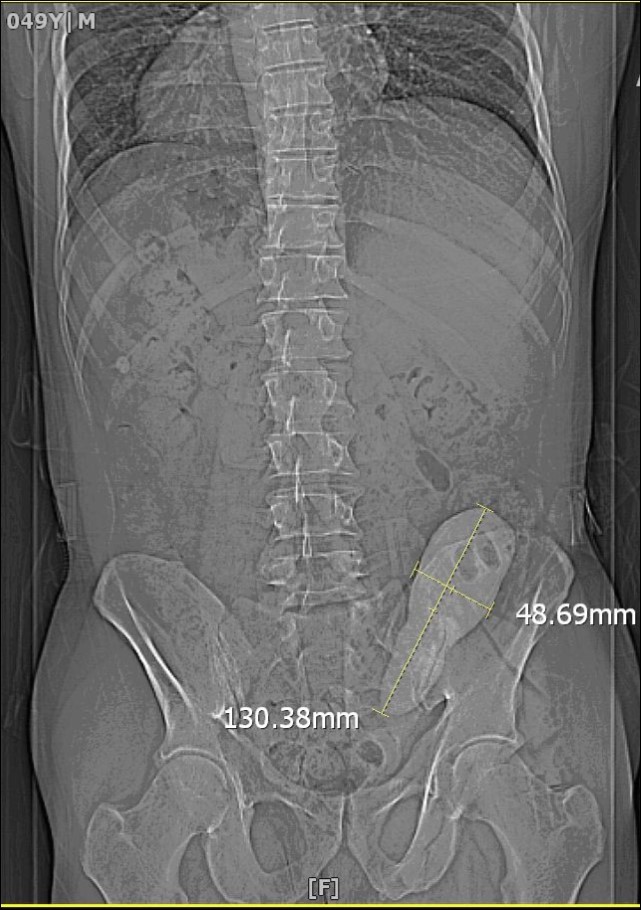

We report a case of a gentleman with spina bifida who underwent urinary diversion in the form of an ileal conduit as a child and presented 40 years later with worsening renal function that was picked up by his general practioner during routing investigations. Clinical examination revealed a hard mass superomedial to the right parararectal stoma. An initial ultrasound scan showed bilateral hydronephrosis and a possible calculus in the conduit. A subsequent CT KUB showed a 13 cm x 4 cm calculus occupying most of the conduit causing outflow obstruction (Figure 1). He also had a 2cm left renal calculus. Following a Foley catheter insertion into the stoma under image guidance, his renal function returned to normality. The patient was counselled for both the open and endoscopic approach.